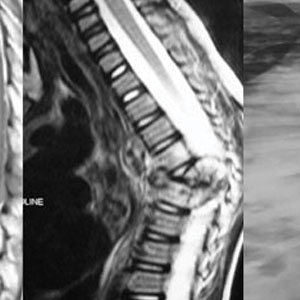

Some of the spinal corrections: